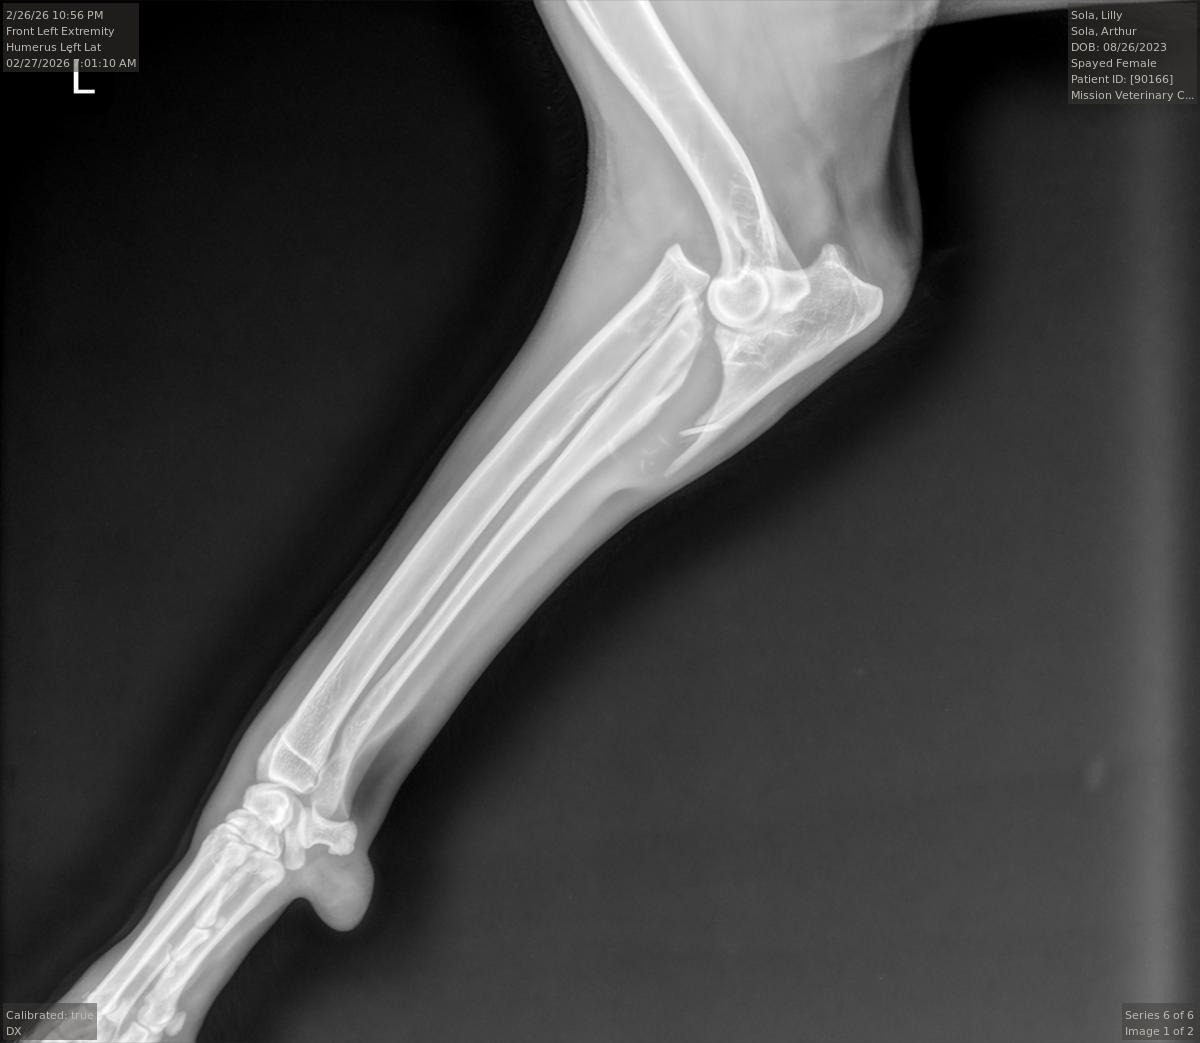

They did the exam and took x-rays and found that her elbow is dislocated and broken and told us she would need orthopedic surgery and that it would be expensive. They also said that they couldn't wrap it or do anything to help it while we worked to get a orthopedic vet appointment. Then told us that the only other options were to amputate her leg (less expensive), or to put her down. This news is crushing my heart, she is only 2 1/2 and an amazing and vibrant girl.

We were able to make an appointment for the orthopedics doctor for this coming Wednesday. Her leg has swollen and we are icing it per the vet's instructions. At the of writing this they are saying we may need to raise around $15,000 to cover the surgery. Please, we are asking for any help we can get to save our girl. Please share this link.